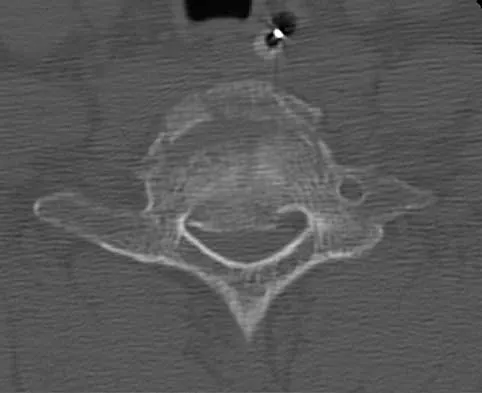

Figure 22 reveals what anatomic variant of the lumbar spine?